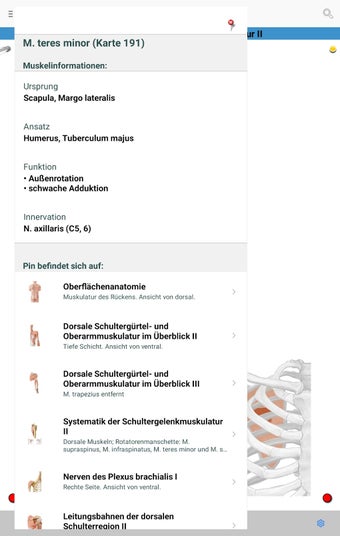

The app consists of different sections, each of which contains information about a specific part of the body. You will learn about the different organs, as well as the muscles, bones, and other important structures. You can test yourself with a unique quiz that consists of multiple-choice questions.